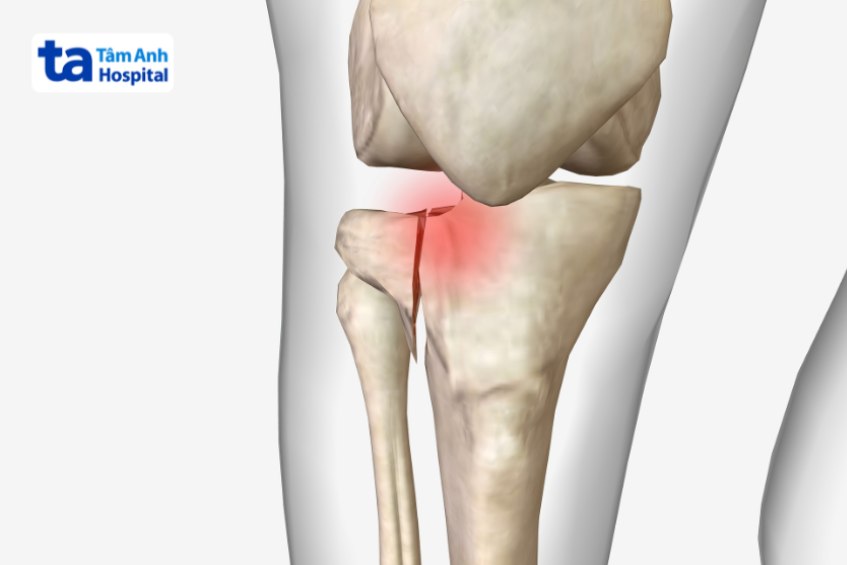

Vỡ mâm chày (gãy mâm chày) là tình trạng mâm chày – phần đầu của xương chày bị vỡ do va đập mạnh hoặc do bệnh lý gây nên. Theo nghiên cứu, gãy mâm chày chiếm khoảng 1,2% trên tổng số ca gãy xương ở người lớn. Tình trạng này gây đau đớn và tổn thương xương khớp nghiêm trọng, khiến người bệnh gặp khó khăn trong công việc và sinh hoạt hằng ngày. (1)

Dưới đây là một số hình ảnh vỡ xương mâm chày: